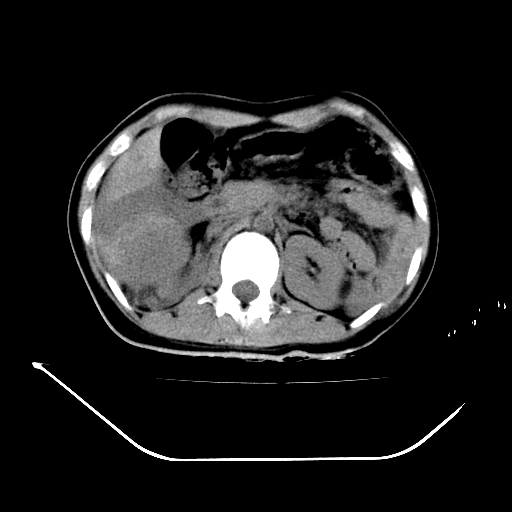

以下是引用liuyue在2008-7-19 13:02:00的发言:[br]1.肝右叶后下段及右肾挫裂伤伴腹腔积血。[br]2.右侧多发性肋骨骨折、横突骨折、右髂骨骨折伴周围软组织挫伤。[br]3.右侧腰大肌肿胀,并可见低密度影,如为气体,则肠道挫裂伤待除外。

以下是引用zhengfaming在2008-7-19 14:42:00的发言:[br]1.肝右叶后下段及右肾挫裂伤伴腹腔积血。脾脏挫裂伤待排[br]2.右侧多发性肋骨骨折、横突骨折、右髂骨骨折伴周围软组织挫伤。[br]3.右侧腰大肌肿胀,并可见低密度影,如为气体,则肠道挫裂伤待除外

以下是引用道哥在2008-7-19 16:52:00的发言:[br]肝右叶后下段及右肾挫裂伤、脾破裂伴腹腔积血。[br]2.双侧多发性肋骨骨折、横突骨折、右髂骨骨折伴周围软组织挫伤。[br]3.右侧腰大肌肿胀,并可见低密度影,如为气体,则肠道挫裂伤待除外。